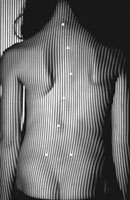

Возможность использования топографического мониторинга состояния больных сколиозом взамен рентгена была изучена на основе клинического материала школы-интерната №133 для детей больных сколиозом г.Новосибирска, где, начиная с 1995 года, проводились ежегодные обследования на ТОДП постоянного контингента больных параллельно с рентгеном. Среди больных по характеру течения заболевания выделены 3 группы: СФ - стабильная форма сколиоза, УПФ - умеренно прогрессирующая, БПФ - быстро прогрессирующая форма. Пример наблюдения больной с быстро прогрессирующей формой сколиоза приведен на рисунках ниже.

9,0 лет 10,4 лет 10,8 лет 11,4 лет 12 лет

PTI=1,0; Cobb=10° PTI=1,3; Cobb=17° PTI=1,9; Cobb=23° PTI=2,9; Cobb=38° PTI=3,6; Cobb=55°

За трехлетний период наблюдения в возрасте с 9 до 12 лет основная правосторонняя грудная дуга по углу Кобба спрогрессировала с 10 до 55°, т.е. средняя скорость прогрессирования составила 15° в год. Общий индекс нарушения формы дорсальной поверхности туловища PTI изменился с 1,0 (граница нормы и умеренно выраженных отклонений) до 3,6 (значительное отклонение). Следует обратить внимание, что в начале наблюдения туловище больной имело хороший баланс во фронтальной плоскости (вертикальная ось, проходящая через вершину межъягодичной складки, проходит также и через C7), а с возраста 10,8 лет стало явно нарастать нарушение баланса с отклонением туловища вправо, т.е. в сторону выпуклости основной дуги. Приведенный пример убедительно демонстрирует наглядность топографических данных и их большую информативность для решения задачи неинвазивного мониторинга состояния больных сколиозом.